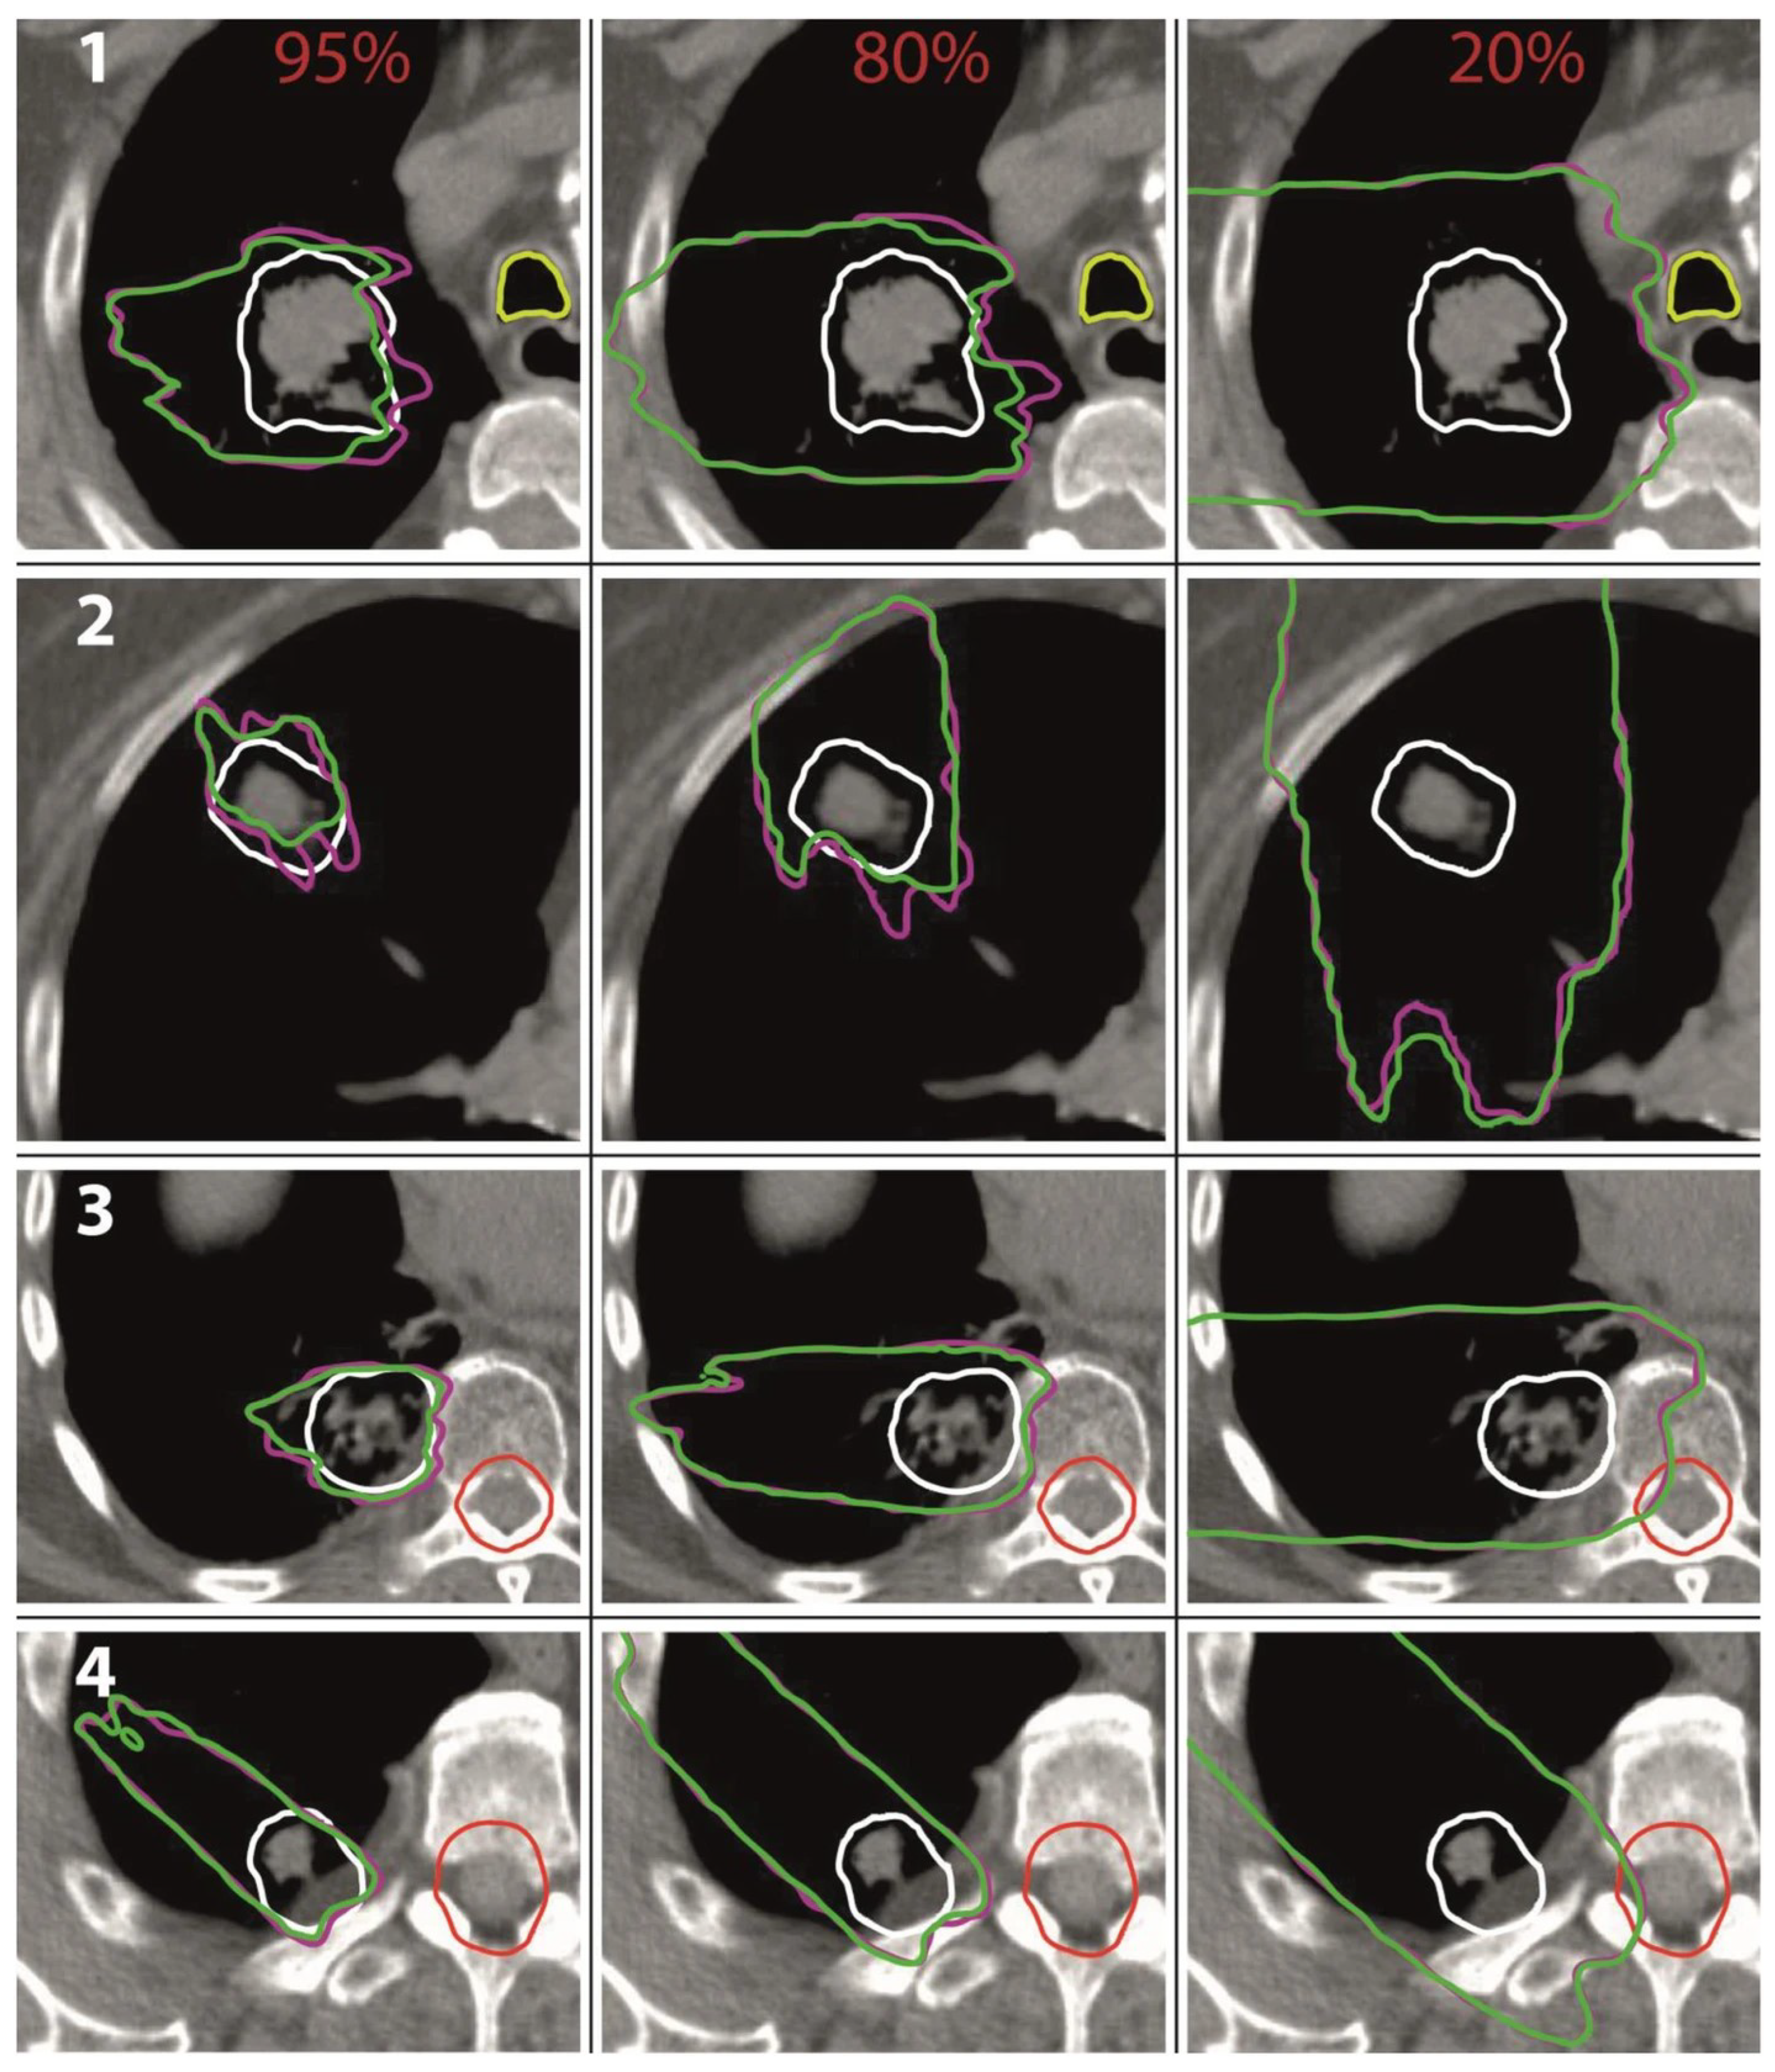

Analogue to the study from Flatten et al. [15], all treatment plans were subsequently recalculated in Monte Carlo simulations with and without modulating the density of the lung voxels. The effects of the lung modulation were investigated for modulation power values of 100 μm, 250 μm, 450 μm, and 800 μm. Again, it was shown that the lung modulation led to an underdosage of the PTV if not accounted for during treatment planning. The effect increased with an increasing modulation power, an increasing depth of the tumor in the lung, and a decreasing tumor volume. For a modulation power of 800 μm, the underdosage in terms of the average dose D mean in the PTV was at most 5%. For a more realistic modulation power of 450 μm, the underdosage was at most 3% and only 1% on average. Additionally, it was shown that for all investigated treatment plans, the passing rate of the Gamma index analysis (3%/1 mm) was a minimum of 90.4% and 96.8% on average for a modulation power of 800 μm. For a modulation power of 450 μm, the passing rate was a minimum of 93.1% and 98.5% on average. The authors further investigated the shift of isodose lines [57,58] for 95%, 80%, and 20% of the prescribed dose (see Figure 10). For the modulated case representing the dose distribution in the patient, the regions enclosed by the 80% and 95% isodose lines were smaller compared to the non-modulated case, demonstrating the underdosage of the target volume. The range uncertainties of the isodose lines in lung tissue were at most 8 mm for the 95% isodose lines and 10 mm for the 85% isodose lines.

The range uncertainties in soft tissue were smaller with only 4 mm and 3 mm, respectively. The 20% isodose lines reached farther for the modulated case demonstrating a potential overdosage of distal normal tissue. The range uncertainties were within 5 mm in lung tissue and 2 mm in soft tissue. No significant increase in the dose deposited to organs at risk could be seen in any of the investigated treatment plans.